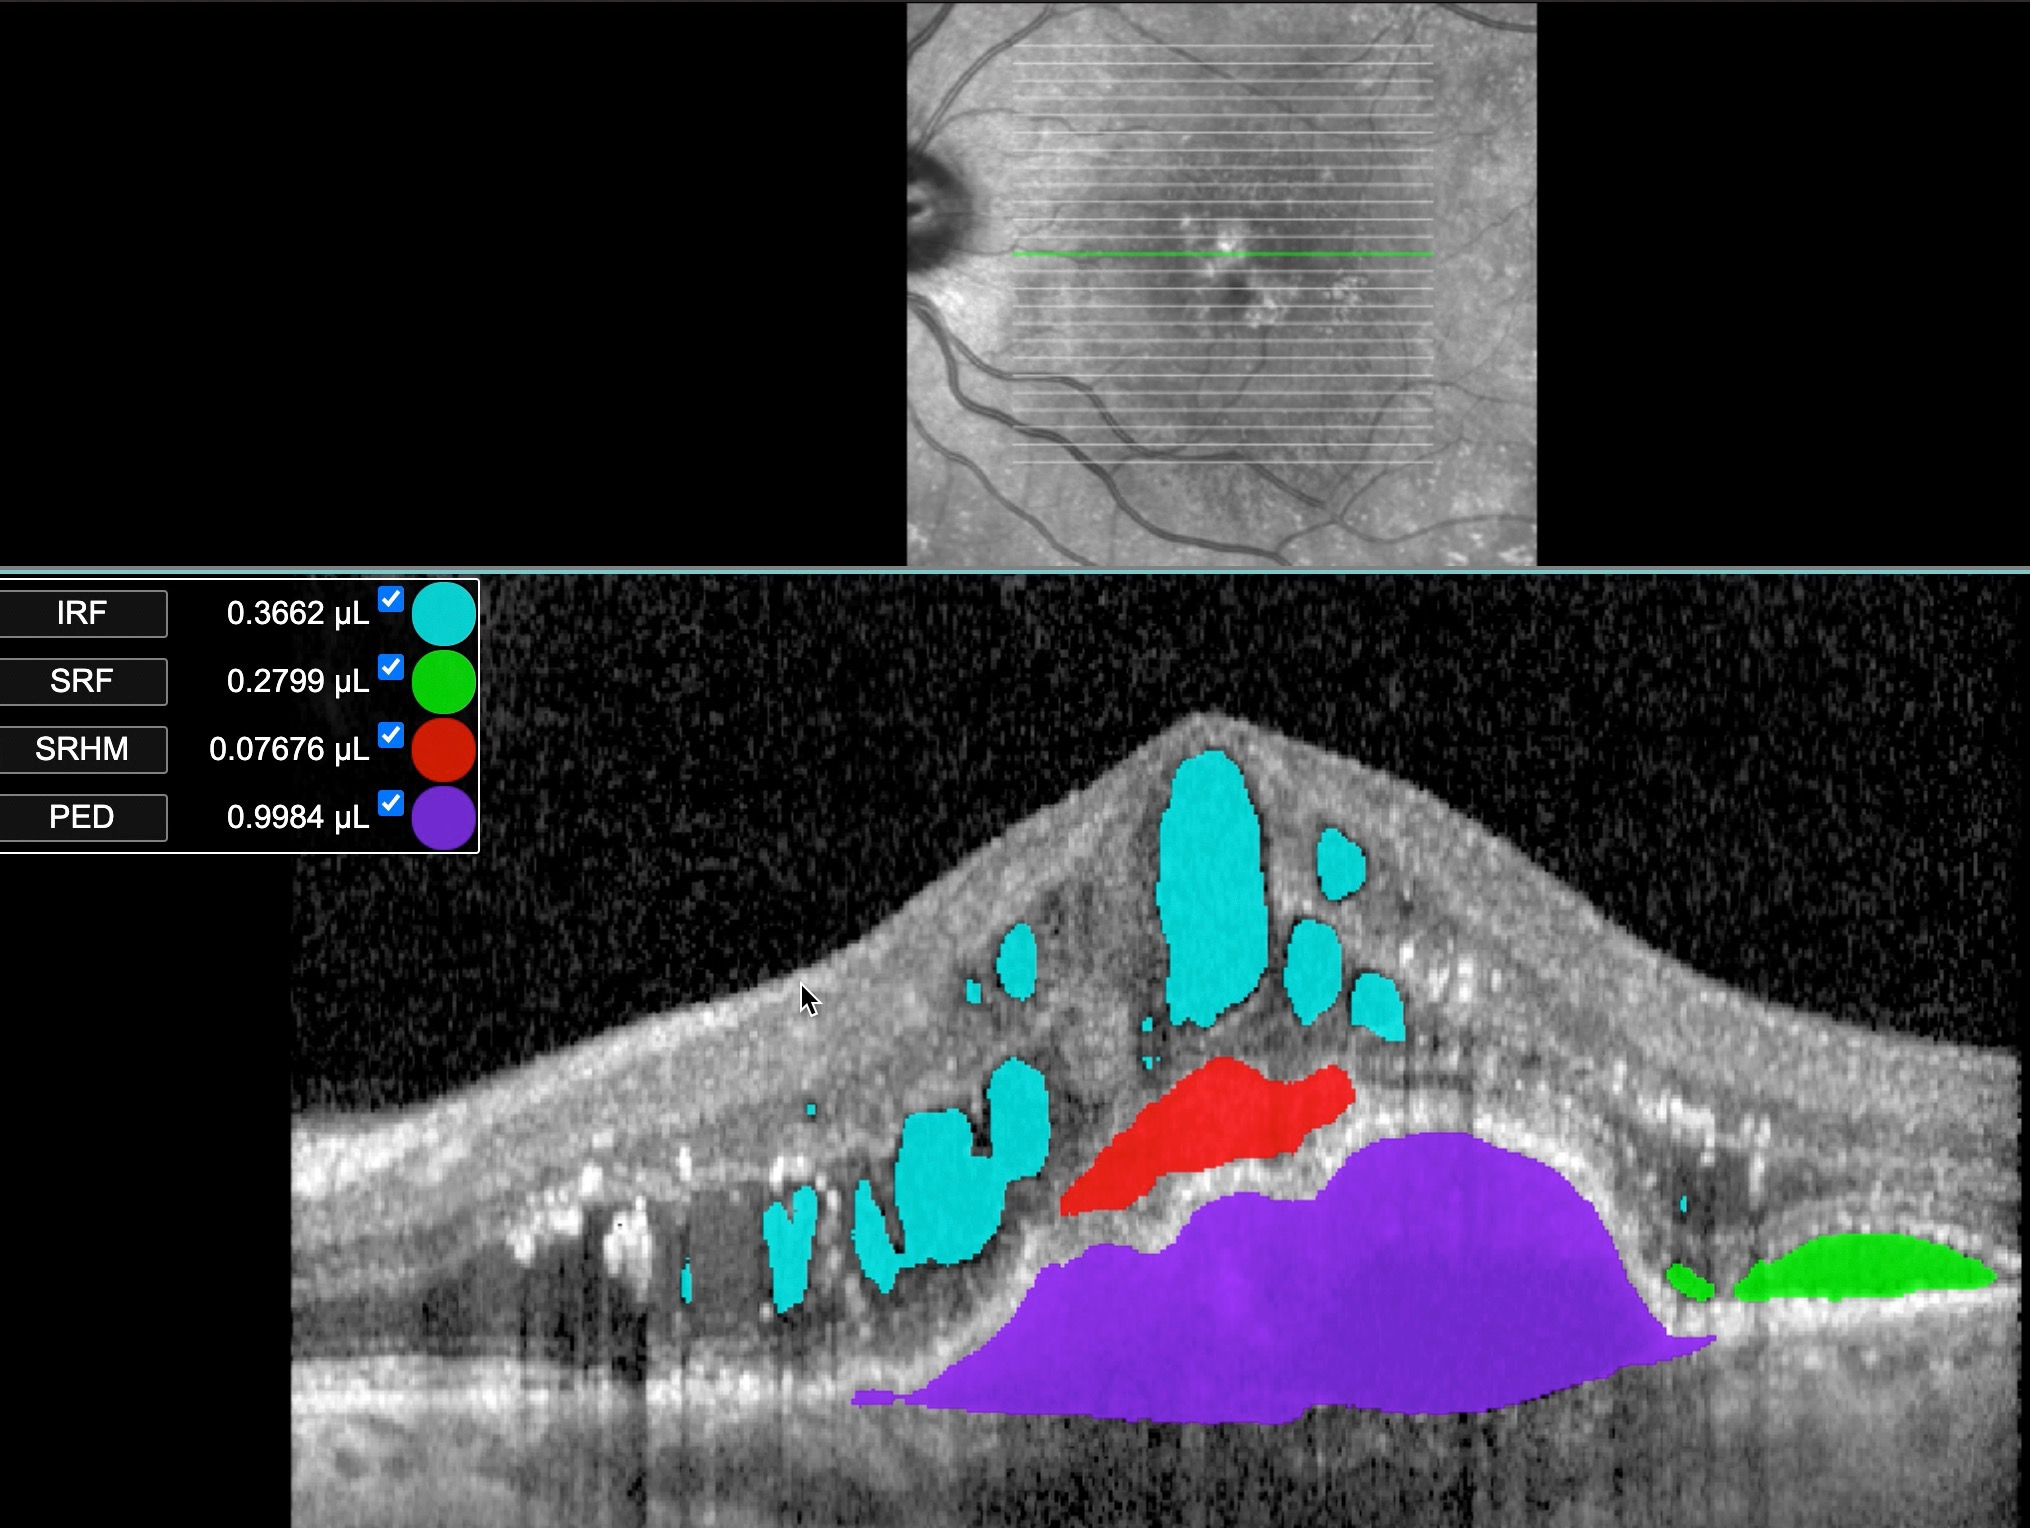

NEO - Neovascular AMD and diabetic macular oedema model

Our NEO segmentation algorithm is applied to Optical Coherence Tomography (OCT) b-scans acquired with the Heidelberg Spectralis. It was trained on our dense segmentation dataset, consisting of manually segmented full volume OCT scans from both TopCon 3D-2000 and Heidelberg Spectralis OCTs. Entire OCT volumes where manually double graded by expert graders at the Moorfields Reading Centre (all 128 b-scans of each TopCon OCT and all 49 b-scans of each Heidelberg OCT), to generate the training data for the NEO model. It is able to segment and quantify the following features of neo-vascular AMD:

• Pigment epithelium detachment (PED)

• Subretinal hyper-reflective material (SHRM)

• Subretinal fluid (SRF)

• Intra retinal fluid (IRF)